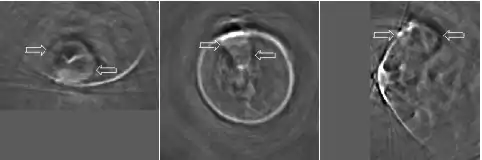

Fig. 2: First 3D thermoacoustic image of breast cancer. From left to right: axial, coronal and sagittal views of the cancer (arrows).

Thermoacoustic imaging was originally proposed by Theodore Bowen in 1981 as a strategy for studying the absorption properties of human tissue using virtually any kind of electromagnetic radiation.[1] But Alexander Graham Bell first reported the physical principle upon which thermoacoustic imaging is based a century earlier.[2] He observed that audible sound could be created by illuminating an intermittent beam of sunlight onto a rubber sheet. Shortly after Bowen's work was published, other researchers proposed methodology for thermoacoustic imaging using microwaves.[3] In 1994 researchers used an infrared laser to produce the first thermoacoustic images of near-infrared optical absorption in a tissue-mimicking phantom, albeit in two dimensions (2D).[4] In 1995 other researchers formulated a general reconstruction algorithm by which 2D thermoacoustic images could be computed from their "projections," i.e. thermoacoustic computed tomography (TCT).[5] By 1998 researchers at Indiana University Medical Center[6] extended TCT to 3D and employed pulsed microwaves to produce the first fully three-dimensional (3D) thermoacoustic images of biologic tissue [an excised lamb kidney (Fig. 1)].[7] The following year they created the first fully 3D thermoacoustic images of cancer in the human breast, again using pulsed microwaves (Fig. 2).[8] Since that time, thermoacoustic imaging has gained widespread popularity in research institutions worldwide.[9][10][11][12][13][14][15] As of 2008, three companies were developing commercial thermoacoustic imaging systems – Seno Medical,[16] Endra, Inc.[17] and OptoSonics, Inc.[18]